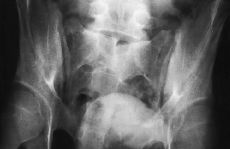

Varón de 18 años trasladado de otro hospital tras sufrir un accidente de tráfico al colisionar la motocicleta en que viajaba con un coche. A su llegada al primer centro hospitalario las constantes vitales fueron: pulso de 70/min, presión arterial de 100/60 mmHg y frecuencia respiratoria de 18/min. El paciente presentaba traumatismo craneoencefálico con hematoma en antifaz y una puntuación de 11/15 en la escala de Glasgow; tumefacción, deformidad y herida puntiforme en ambos codos; hematoma escrotoinguinal y separación pubiana de 6-8 cm; no existía déficit neurológico ni vascular en las extremidades inferiores, el tono rectal era normal y la orina tras sondaje vesical era clara. En los exámenes radiográficos se apreció fractura de olécranon derecho e izquierdo, con luxación anterior de codo izquierdo, diástasis pubiana y fractura longitudinal de sacro (Fig. 1). La ecografía abdominal fue normal. En la tomografía axial computerizada (TAC) craneal se diagnosticó edema cerebral con colapso ventricular y hematoma epidural frontal izquierdo de 2 cm.

Figura 1. Radiografía anteroposterior de la pelvis realizada al ingreso del paciente en la que se aprecia diástasis pubiana de 6 cm, fractura longitudinal del cuerpo del sacro, espina bífida oculta a partir de S3 y apertura de la articulación sacroilíaca izquierda.